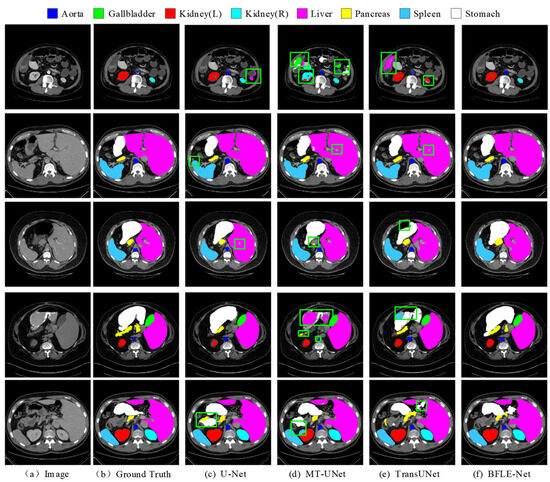

In this study, the performance of various segmentation methods, including U-Net, MT-UNet, TransUNet, and BFLE-Net, is systematically compared on the Synapse and ACDC datasets. The experimental results reveal significant performance differences among the methods in segmenting complex anatomical structures. As shown in Figure 6, in the multi-organ segmentation task on the Synapse dataset, both U-Net and MT-UNet suffer from considerable over-segmentation, particularly in the stomach region, where organ misclassification occurs. More notably, MT-UNet and TransUNet exhibit substantial topology confusion in the segmentation of the left and right kidneys, as well as inaccuracies in localizing the spatial relationship between the gallbladder and the liver. These issues highlight that current methods still face significant challenges in incorporating anatomical prior knowledge and modeling 3D spatial context dependencies for multiple organs. In contrast, the method proposed in this study substantially improves the completeness of segmentation and effectively addresses the problem of semantic confusion between organs, particularly in distinguishing neighboring organs (e.g., the liver and gallbladder) with similar grayscale features, thus demonstrating significant advantages.

Figure 6. Qualitative analysis results on the Synapse dataset. Note: The green box in the figure indicates the location where the effect of segmentation is insufficient.